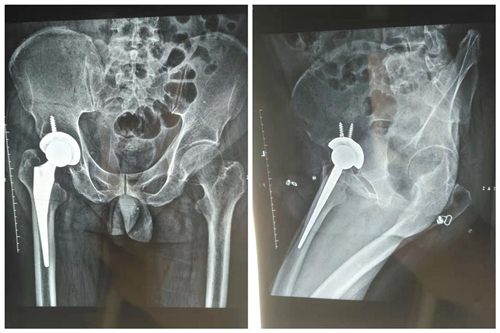

患者术后X线

8月15日,有一名52岁男性患者,癫痫发作摔倒致左髋部疼痛伴活动受限2天,诊断为股骨颈骨折(gardanⅣ型),既往有癫痫病史30余年,每月发作2次左右,最近几年发作频繁,依从性差,考虑拉力空心钉固定术后三个月内不能负重,3-6个月内部分负重,而且股骨头坏死率极高,针对这种具有高脱位风险患者,经过术前缜密计划,充分沟通,决定对患者行前路微创全髋关节置换术(DAA),微创骨科团队独立完成了此项手术,患者一周后康复出院。

前路微创全髋关节置换术(DAA),作为目前人工全髋关节置换术中唯一的神经肌肉间隙入路。有软组织损伤小,术后恢复快,脱位率低以及术后髋关节活动几乎不受限制等诸多优势。并且平卧位手术更容易控制假体安装和下肢长度。可以使用任何厂家产品,因为它良好的初始稳定性,理想的患者满意度,欧美及日本在初次全髋置换中所占比越来越高。同时,也因为它的学习曲线较长,难度大,技术要求极高,而在我国仅1—2%应用率。目前在我国大概仅有3%左右骨科医生掌握DAA入路,而且大多是骨科实力雄厚的大医院。